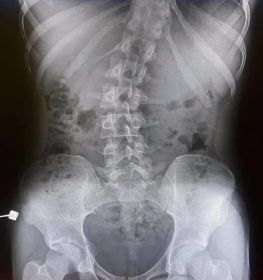

Omurga eğriliği yaşan insanlarda eğer eğrilik 40 dereceyi aşmış ise cerrahi operasyon ile tadavi edilir. Bu şekilde bir tedavi çok riskli ve zordur. Ardından ise mutlaka fizik tedavi ek olarak da korse tedavisi uygulanmalıdır.

Skolyoz hastalığı omurgaların dizilimindeki düzensizlik ve yamukluktur. Çoğunlukla çocuklukta görülen hastalık yetişkinlerde de az da olsa görülebilir. Sağa sola omurgalardaki çıkıntıların zamanla omurilik eğriliği bir hale getirdiği hastalıkta erken tanı çok önemlidir. İster yetişkin isterse çocuk olsun erken teşhis sonucunda fizik tedavi yöntemi işe yarar. Hastalık özellikle kişilerin günlük yaşantılarını etkileyen olumsuzluklar yaşatan ve yaşam kalitesini düşüren bir rahatsızlıktır. Geç kalınmadan tedaviye başlanmalıdır.